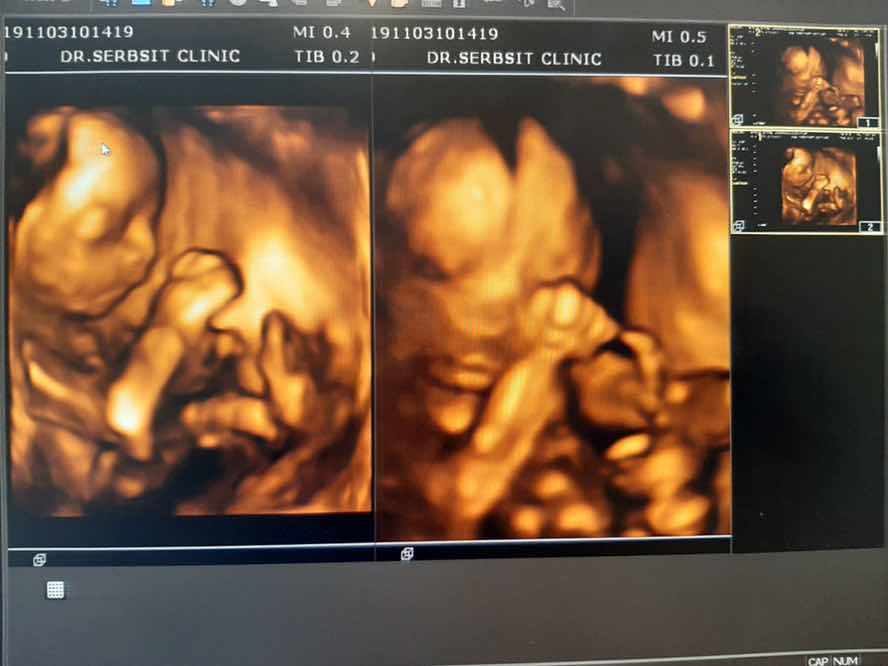

ซาวตอน5 เดือนค่ะ

ช่วง5เดือนกว่าค่ะ

5 เดือน 4 มิติค่ะ